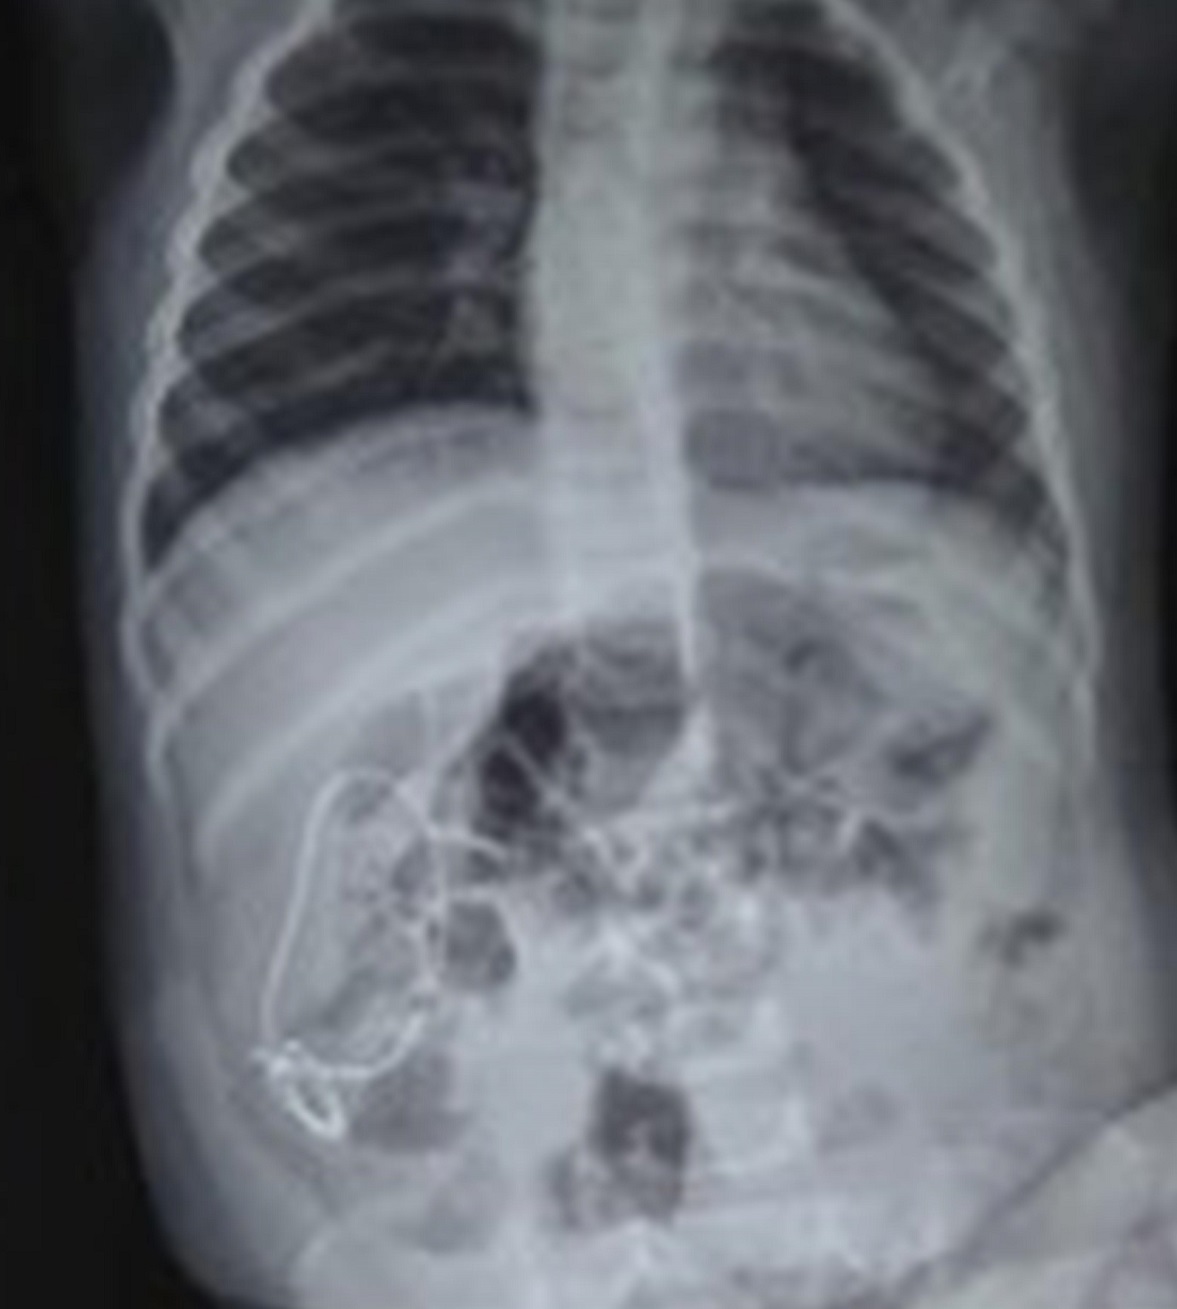

Proximal Migration of Ureteric DJ Stent: A Case Series

Background: DJ stents are routinely used in urological procedures. Rarely these may dislodge or migrate.

Case Series: Here we report proximal migration of DJ stent in three children with pelvi-ureteric junction (PUJ) obstruction treated with dismembered pyeloplasty. Ureteroscopy and retrieval of migrated DJ stents were performed in each of these patients.

Conclusion: Proximal migration of DJ stent, though rare, can cause significant morbidity and complicates it’s removal. Proper size and positioning of stent is required for pediatric patients.